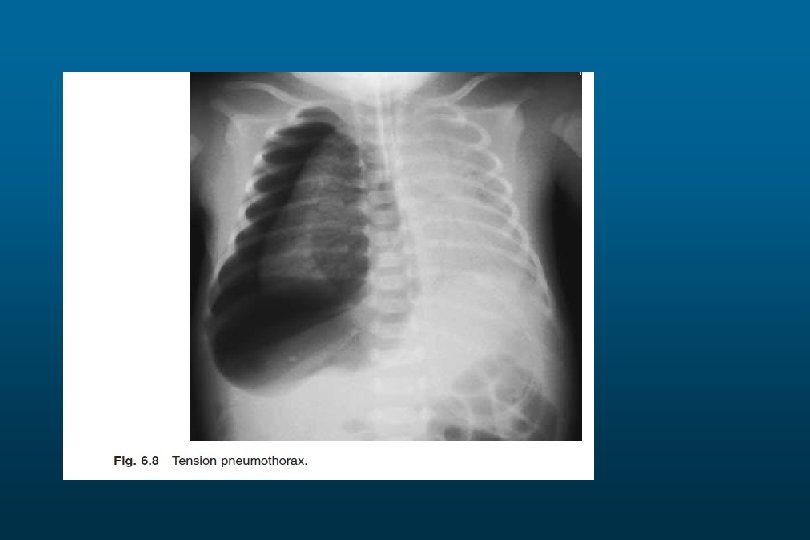

Pneumothorax